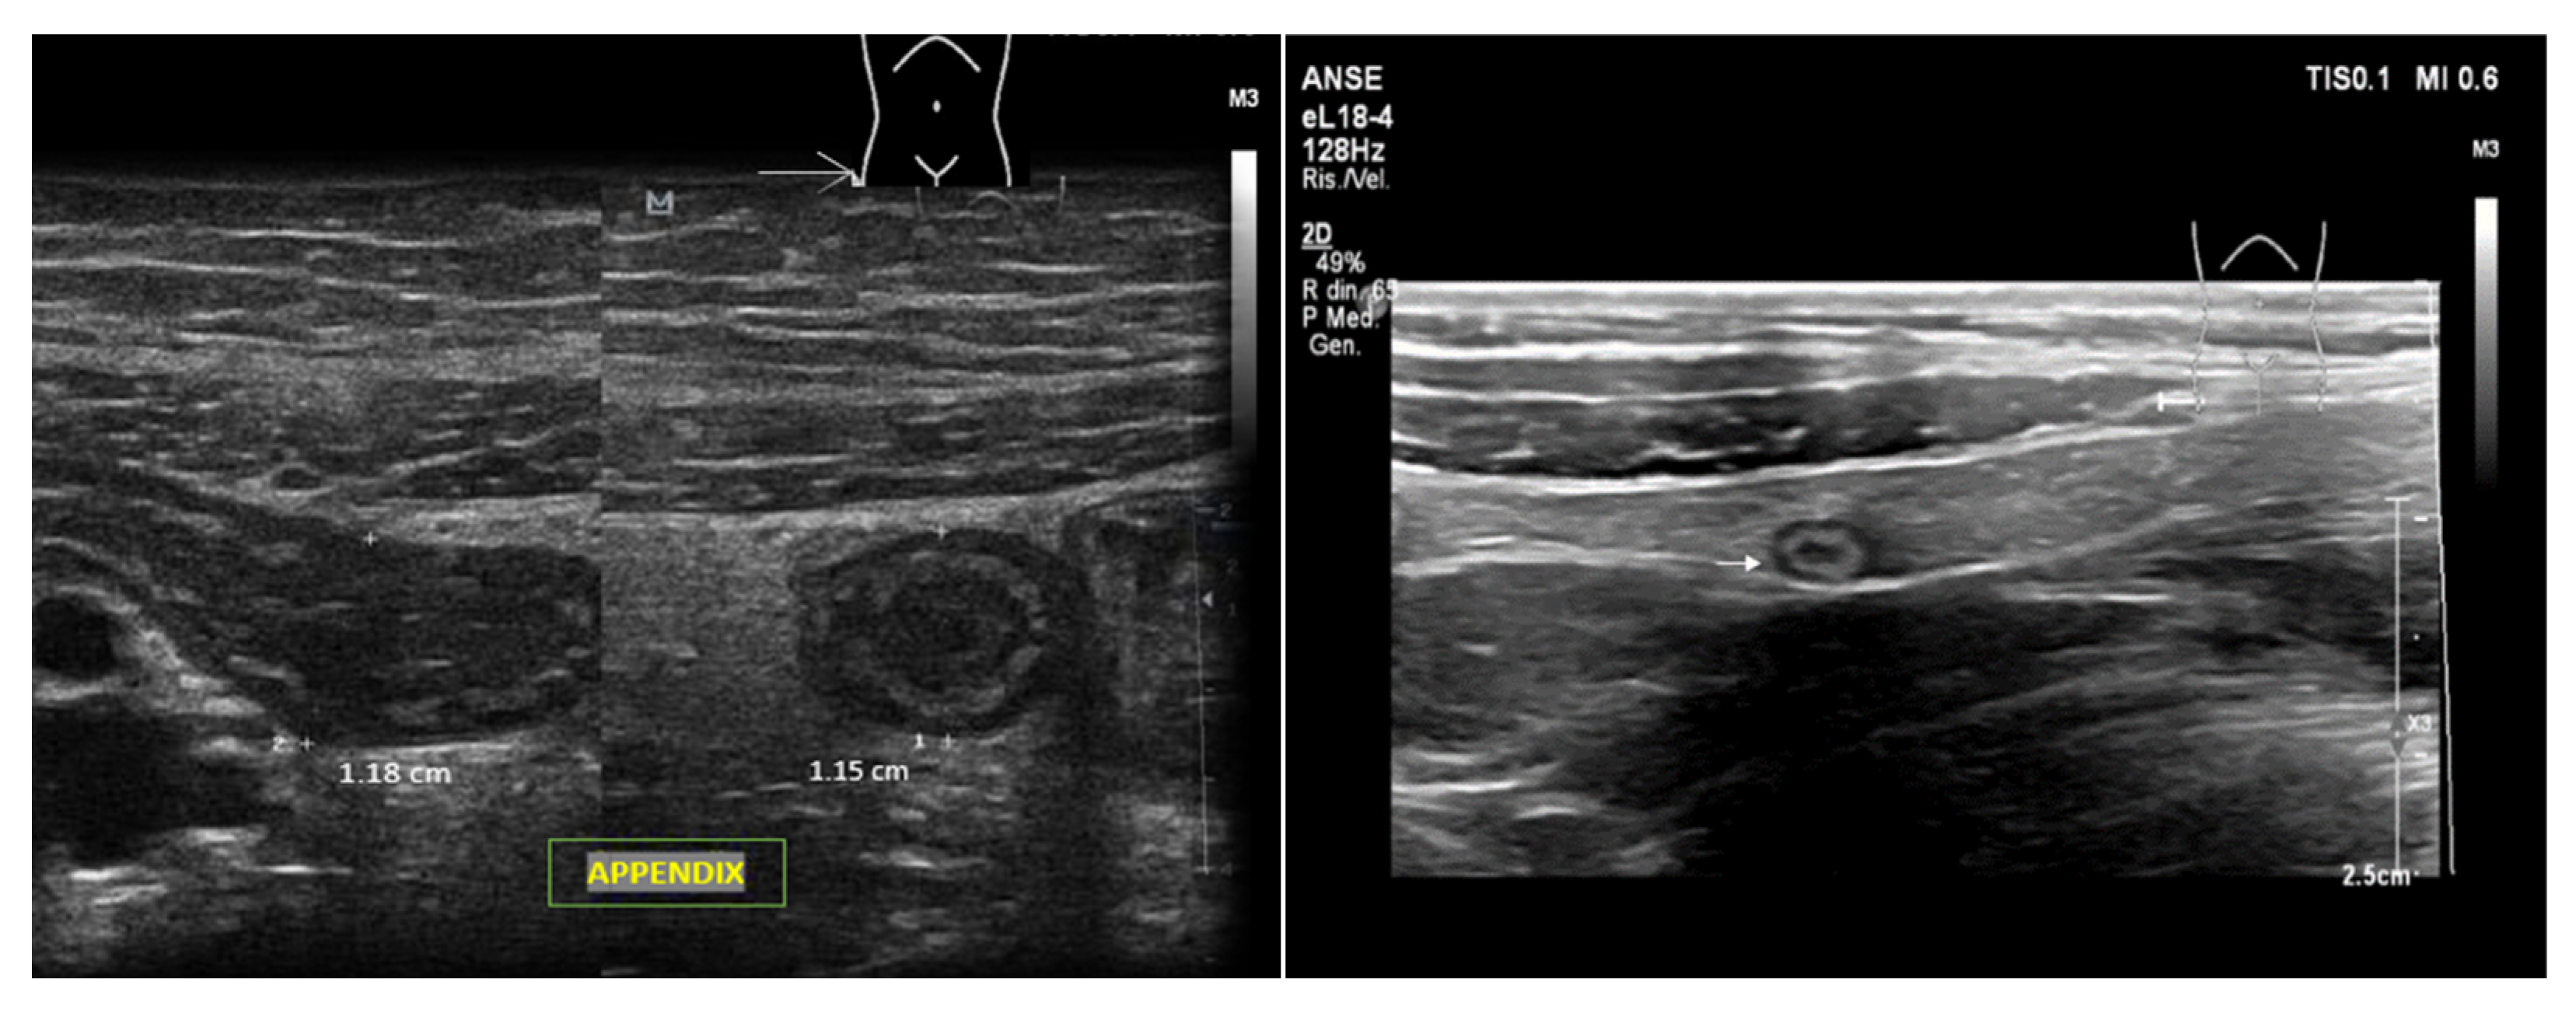

5. Deep-Vein Thrombosis

5.1. Protocol

5.2. Imaging

- Acute: the thrombus itself may not be visible. If detected, it is deformable with the force applied on the probe and with a regular surface; it is a distended vein.

- Subacute thrombus: (before six months and after clot formation) intermediate morphological changes that cannot be included in the chronic phase.

- Chronic post-thrombotic change: not compressible nor deformable with an irregular surface; the vein caliber may be normal or reduced.